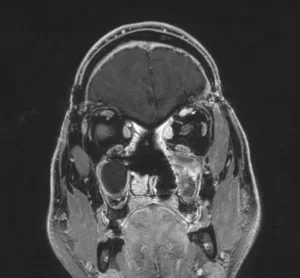

Ασθενής άνδρας, 44 ετών με διαταραχές προσωπικότητας, κεφαλαλγίες και ανοσμία. Επείγουσα εισαγωγή λόγω απώλειας όρασης και βυθιότητας.

Η αξονική και μαγνητική τομογραφία εγκεφάλου ανέδειξε γιγαντιαία εξεργασία στον πρόσθιο κρανιακό βόθρο με σημαντική επέκταση εντός της ρινικής κοιλότητας και διήθηση των οφθαλμικών κόγχων, κυρίως αριστερά.

Ο ασθενής υπεβλήθη σε αμφιμετωπιαία κρανιοτομία καθώς επίσης και σε ενδοσκοπική διαρρινική αφαίρεση της βλάβης. Η ιστολογική εξέταση ανέδειξε αισθησιονευροβλάστωμα.

Μετεγχειρητικά σαφής βελτίωση της όρασης και των λοιπών συμπτωμάτων.

Ο συγκεκριμένος όγκος είναι εξαιρετικά εκτεταμένος και αποτελεί σε κάθε περίπτωση μια χειρουργική πρόκληση. Ο συνδυασμός κρανιοτομίας και ενδοσκοπικής διαρρινικής προσπέλασης επέτρεψε την αφαίρεση της βλάβης. Σε περιπτώσεις σαν και αυτή, το έλλειμα στη βάση του κρανίου μετά την αφαίρεση του όγκου είναι ιδιαίτερα εκτεταμένο και πρέπει να υπάρχει σαφές σχέδιο αποκατάστασης της βάσης του κρανίου με συνδυασμό αυτόλογων και ετερόλογων μοσχευμάτων.